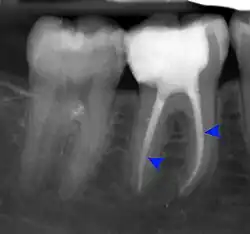

Apical periodontitis is acute or chronic inflammation around the apex of a tooth caused by an immune response to bacteria within an infected pulp.[20] It does not occur because of pulp necrosis, meaning that a tooth that tests as if it's alive (vital) may cause apical periodontitis, and a pulp which has become non-vital due to a sterile, non-infectious processes (such as trauma) may not cause any apical periodontitis.[10]: 225 Bacterial cytotoxins reach the region around the roots of the tooth via the apical foramina and lateral canals, causing vasodilation, sensitization of nerves, osteolysis (bone resorption) and potentially abscess or cyst formation.[10]: 228

The periodontal ligament becomes inflamed and there may be pain when biting or tapping on the tooth. On an X-ray, bone resorption appears as a radiolucent area around the end of the root, although this does not manifest immediately.[10]: 228 Acute apical periodontitis is characterized by well-localized, spontaneous, persistent, moderate to severe pain.[6]: 125–135 The alveolar process may be tender to palpation over the roots. The tooth may be raised in the socket and feel more prominent than the adjacent teeth.[6]: 125–135

- Radiographs utilized to find dental caries and bone loss laterally or at the apex.